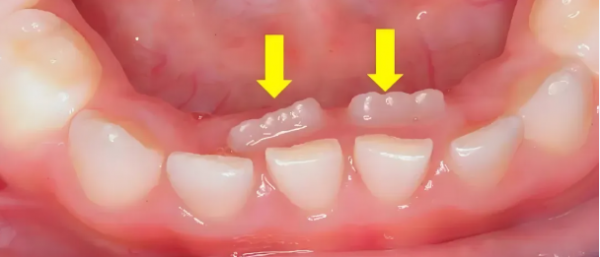

正常情况下,孩子的乳牙会在6-12岁期间逐渐脱落,为恒牙让出位置。当乳牙尚未脱落,而恒牙已经从牙龈内侧或外侧萌出时,就形成了“双排牙”。

这种现象最常见于下前牙区域,其次是上前牙区域。数据显示,近年来儿童双排牙的发病率显著上升,已成为儿童口腔科的常见问题。